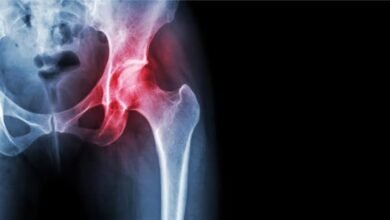

تعرف على التهاب مفصل الورك

آيسك نيوز.. الصورة تشير إلى التهاب مفصل الورك، وغالبًا ما يكون ناتجًا عن خشونة أو تآكل الغضروف، مما يؤدي إلى…